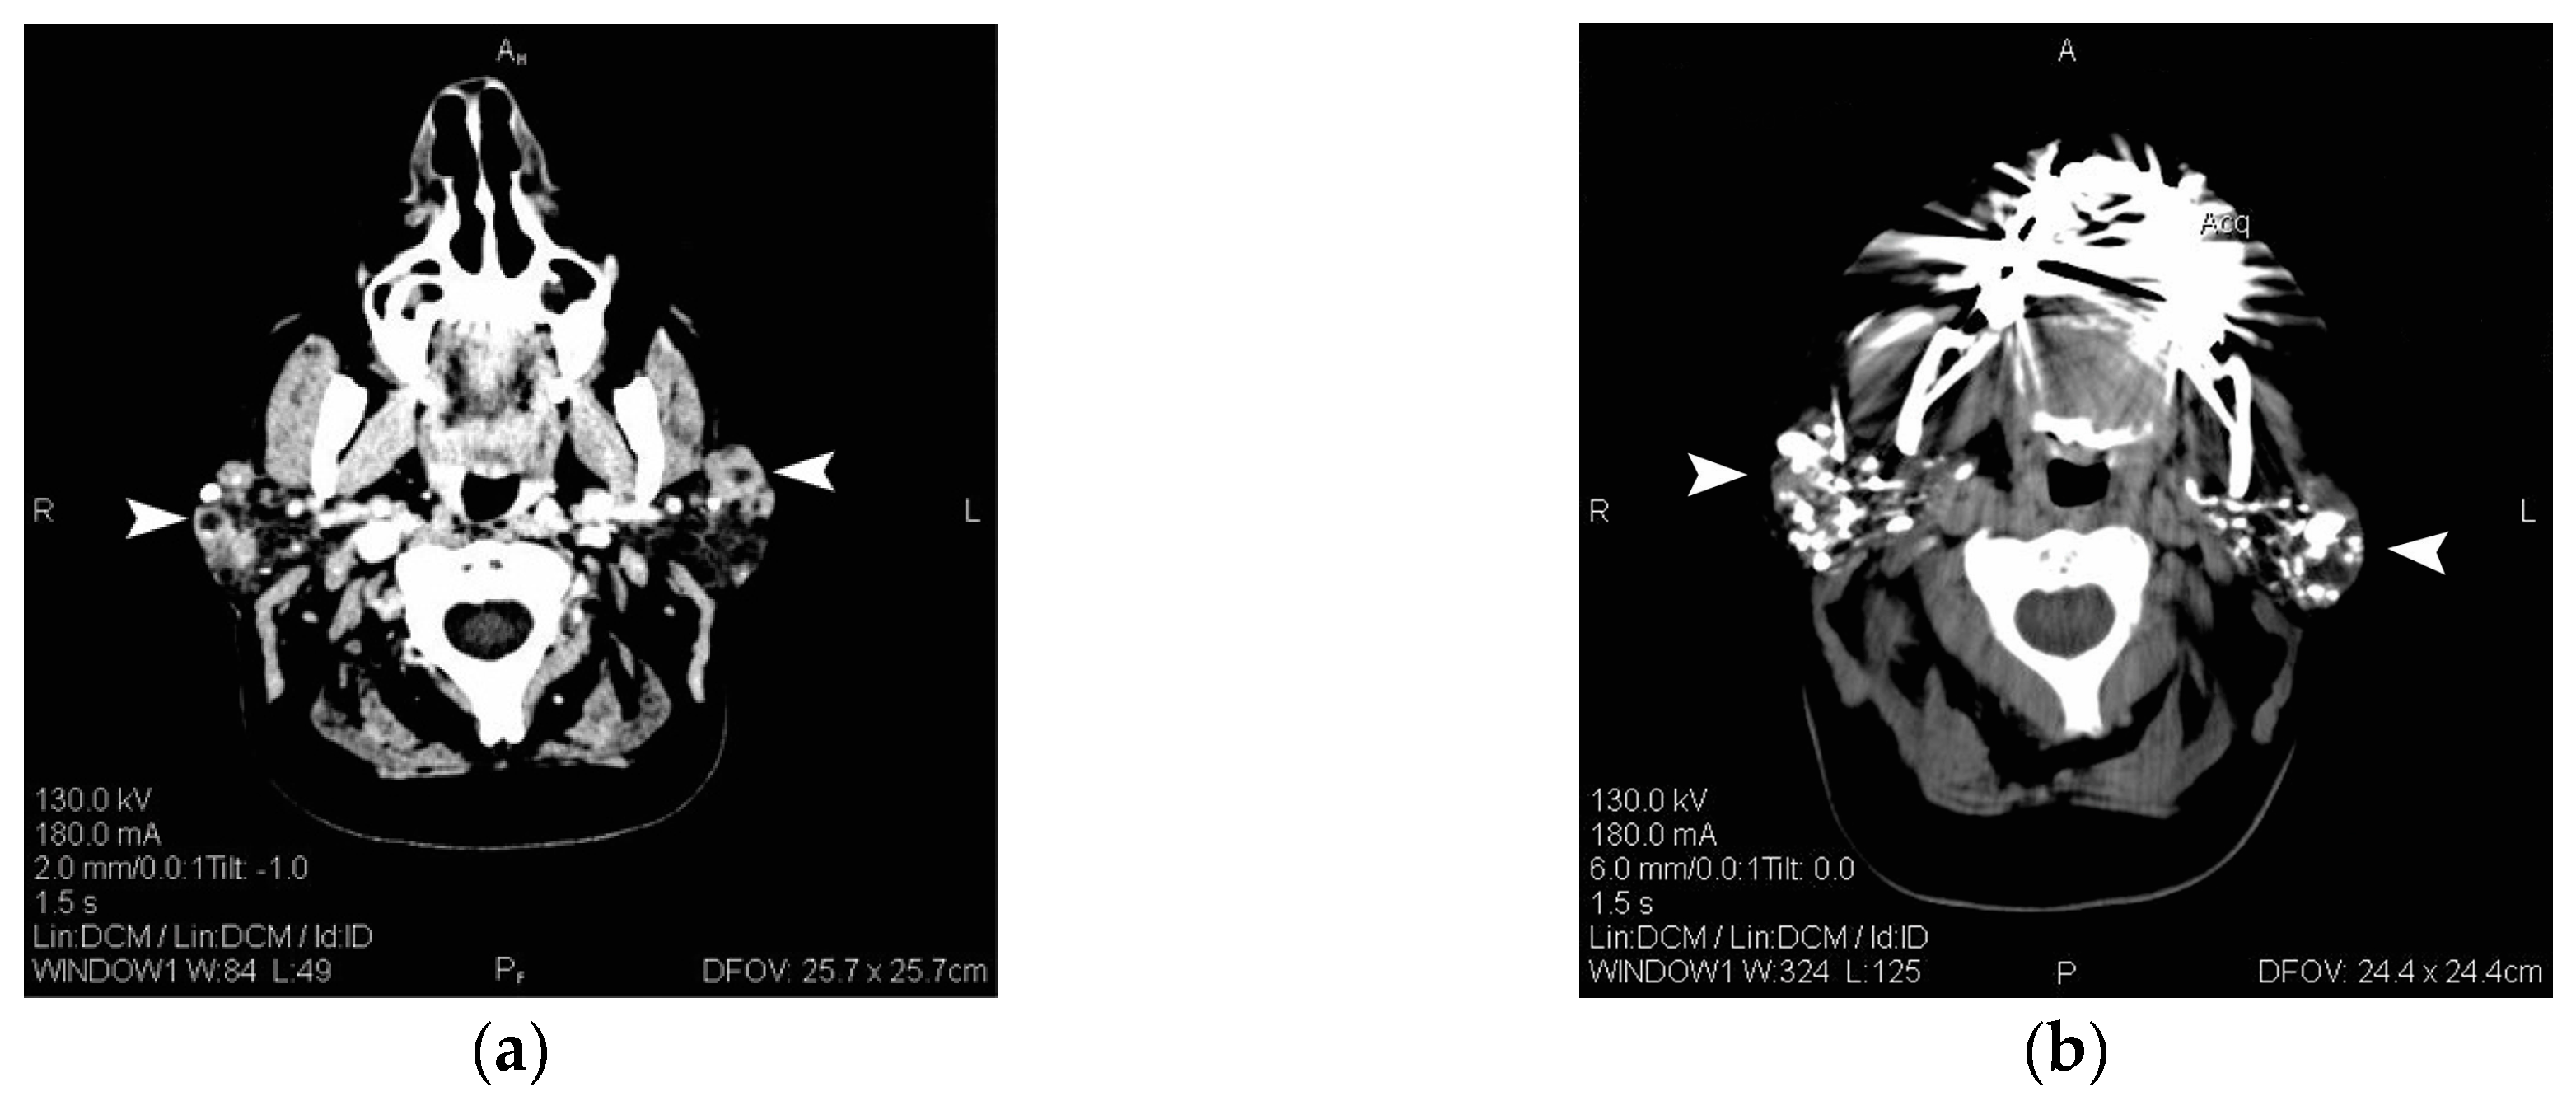

We report the case of a 58-year-old female patient, with no significant disease history, except for a slow growing mass on her left mandible, which became stiffer over time. The patient did not report any symptoms associated with impaired function of the salivary or lacrimal glands. She was referred to a surgery department and, after raising the suspicion of a PG tumor, a computed tomography (CT) scan was performed. On CT scans, both PGs displayed pronounced structural abnormalities with predominant cystic transformation and multiple calcifications (Figure 1a), while on the CT sialography marked sialectasis, of over 7 mm bilaterally, and no evidence of other potential obstruction in the ductal system were depicted (Figure 1b).

Figure 1.

(a) CT (computed tomography) scan, axial section of the head, both PGs (parotid glands) are enlarged and display structural abnormalities, with multiple cystic formations (arrowheads); (b) CT sialography scan displays bilateral marked sialectasis with quasi-total involvement of glandular parenchyma (arrowheads).